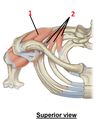

Subscapularis

1? 2?

1: Infraspitanus muscle

2: Teres minor muscle

1?

1: Supraspinatus muscle

1? 2?

1: Supraspinatus muscle

2: Serratus anterior muscle